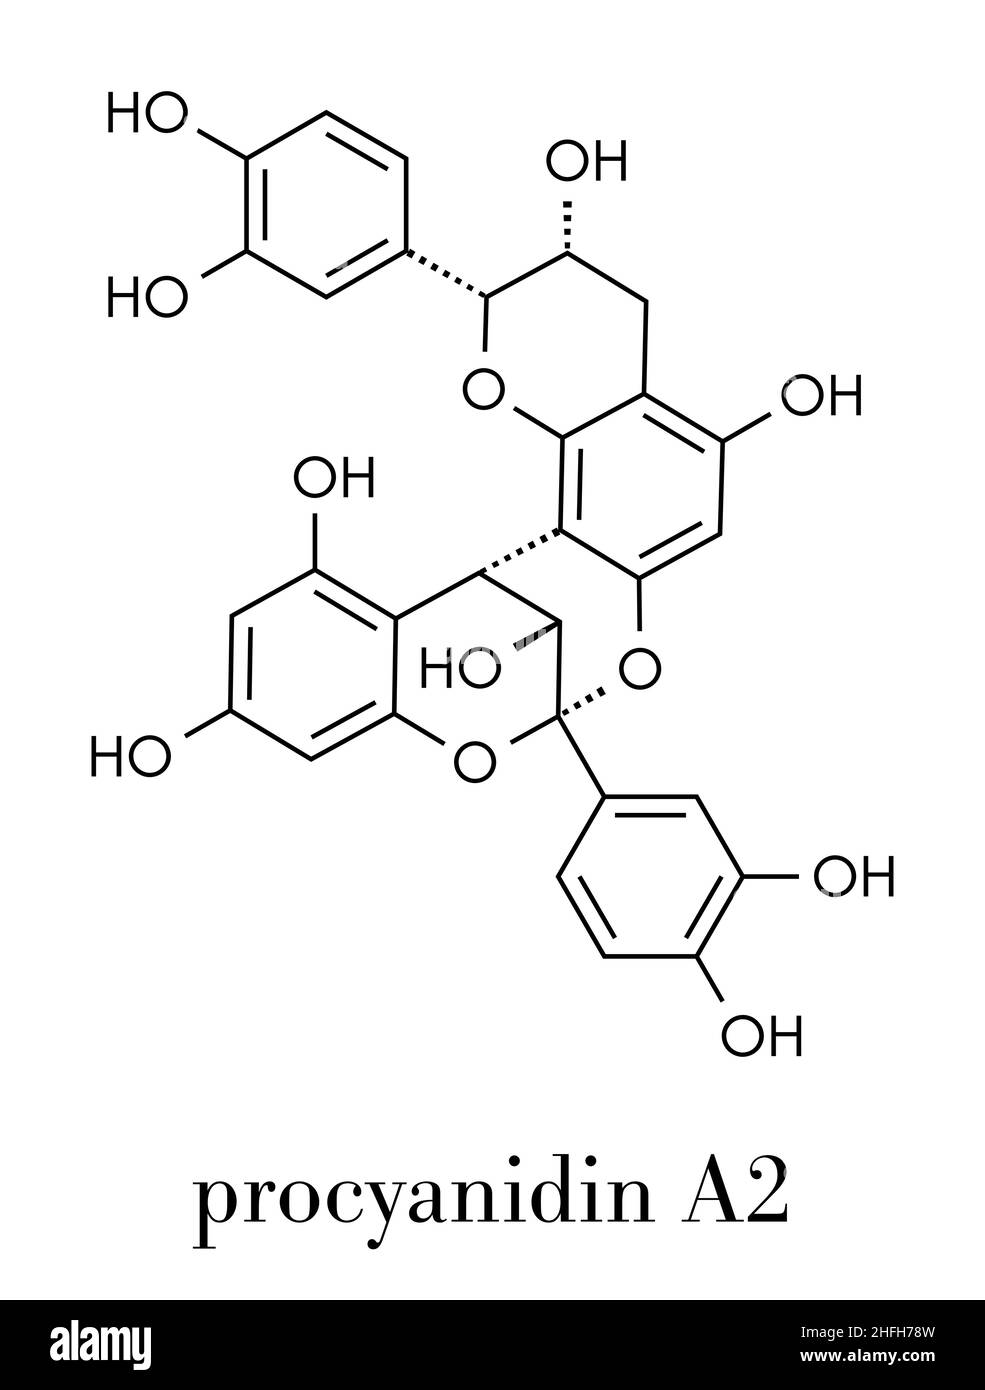

Proanthocyanidin A2 (procyanidin A2, PAC A2) molecule. Present in cranberry (juice) and a number of other plants. Used in urinary tract infarction pre Stock Vectorhttps://www.alamy.com/image-license-details/?v=1https://www.alamy.com/proanthocyanidin-a2-procyanidin-a2-pac-a2-molecule-present-in-cranberry-juice-and-a-number-of-other-plants-used-in-urinary-tract-infarction-pre-image457068329.html

Proanthocyanidin A2 (procyanidin A2, PAC A2) molecule. Present in cranberry (juice) and a number of other plants. Used in urinary tract infarction pre Stock Vectorhttps://www.alamy.com/image-license-details/?v=1https://www.alamy.com/proanthocyanidin-a2-procyanidin-a2-pac-a2-molecule-present-in-cranberry-juice-and-a-number-of-other-plants-used-in-urinary-tract-infarction-pre-image457068329.htmlRF2HFH78W–Proanthocyanidin A2 (procyanidin A2, PAC A2) molecule. Present in cranberry (juice) and a number of other plants. Used in urinary tract infarction pre

Proanthocyanidin A2 (procyanidin A2, PAC A2) molecule. Present in cranberry (juice) and a number of other plants. Used in urinary tract infarction pre Stock Vectorhttps://www.alamy.com/image-license-details/?v=1https://www.alamy.com/proanthocyanidin-a2-procyanidin-a2-pac-a2-molecule-present-in-cranberry-juice-and-a-number-of-other-plants-used-in-urinary-tract-infarction-pre-image457067384.html

Proanthocyanidin A2 (procyanidin A2, PAC A2) molecule. Present in cranberry (juice) and a number of other plants. Used in urinary tract infarction pre Stock Vectorhttps://www.alamy.com/image-license-details/?v=1https://www.alamy.com/proanthocyanidin-a2-procyanidin-a2-pac-a2-molecule-present-in-cranberry-juice-and-a-number-of-other-plants-used-in-urinary-tract-infarction-pre-image457067384.htmlRF2HFH634–Proanthocyanidin A2 (procyanidin A2, PAC A2) molecule. Present in cranberry (juice) and a number of other plants. Used in urinary tract infarction pre